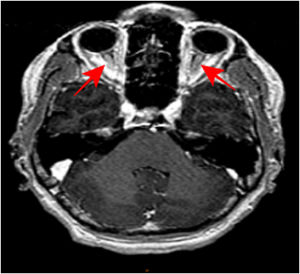

En la resonancia magnética cerebral con contraste se describe una discreta hiperseñal de ambos nervios ópticos más marcada en secuencia T2 (fig. 1) con marcado realce de las lesiones tras la inyección de contraste intravenoso en secuencia 3DT1 (fig. 2). Estos hallazgos son sugestivos de neuritis óptica bilateral. En el resto del estudio por neuroimagen no se objetivaron otras alteraciones (cerebro y médula espinal).